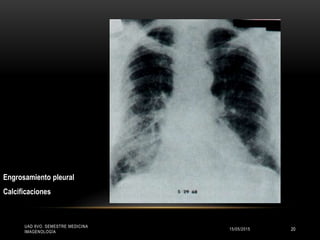

Engrosamiento pleural

Calcificaciones

MANIFESTACIONES CLÍNICAS

Radiografía:

• Opacidades irregulares pequeñas predominantes en los 2/3 inf de los

campos pulmonares.

•Ocasionalmente opacidades redondeadas pequeñas, con engrosamiento

pleural, circunscrito o difuso con calcificaciones, reduciendo la capacidad

vital y los famosos “dedos hipocráticos”